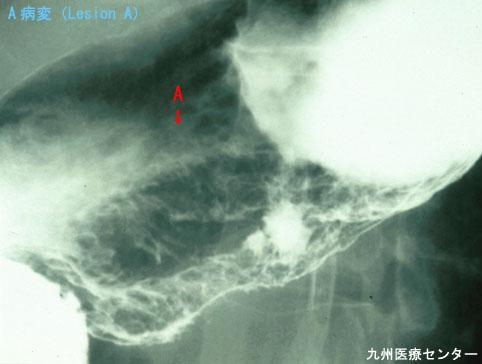

伴有十二指肠腺瘤的胃的绒毛癌(病例提供:国立病院九州癌中心)

[ Image ID:3131 ]

部位(按器官分)

胃(部位)/体部

检查方法

X线

肿瘤的肉眼分类

0型(表在型)/其他

肿瘤最大直径

40以上

肿瘤的深度

m